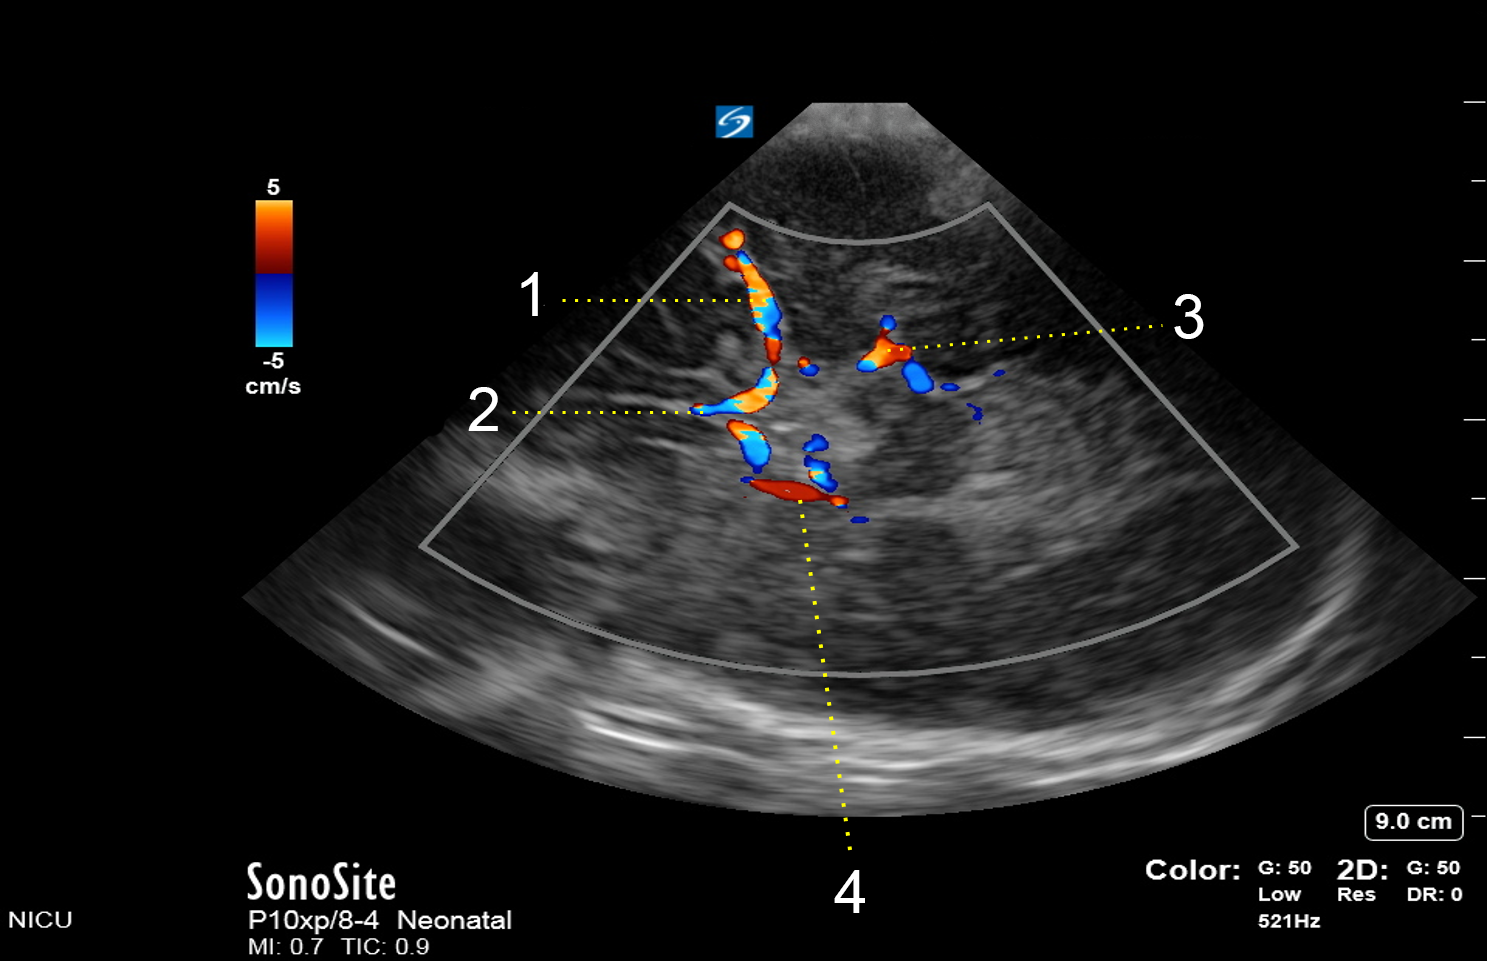

Neonatology Circle of Willis Doppler Image

1. Middle Cerebral Artery (MCA)

2. Anterior Cerebral Artery (ACA)

3. Posterior Cerebral Artery (PCA)

4. Posterior Communicating Artery (PCOM)